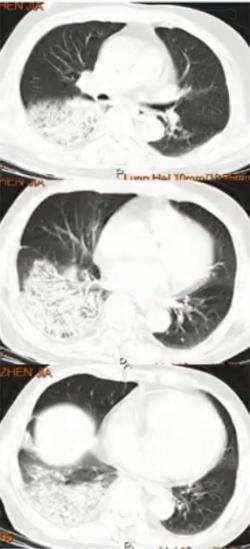

图1 患者的影像学以实变为主

图2 影像表现以多发肺结节合并晕征,类似于真菌感染

图3 双肺弥漫性小结节为主,中下肺布满粟粒样小结节,部分融合成片状